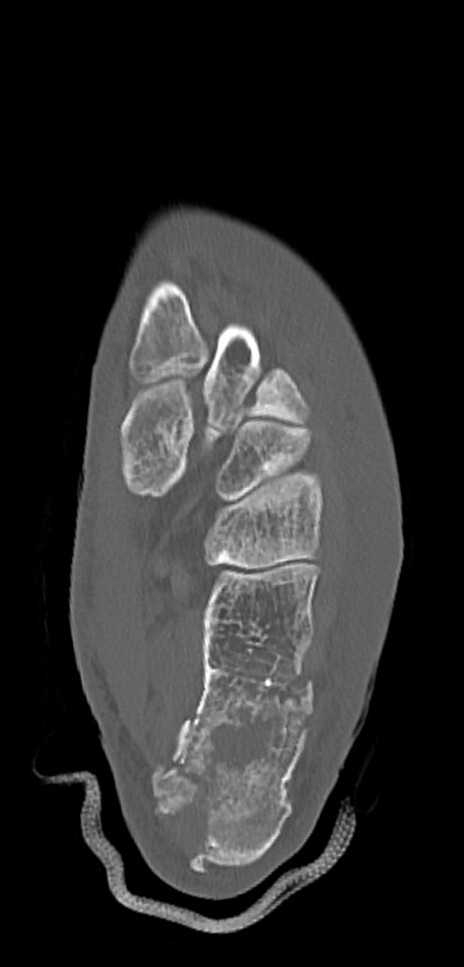

症例37 左足関節CT(横断像)

左足関節CT

冠状断像